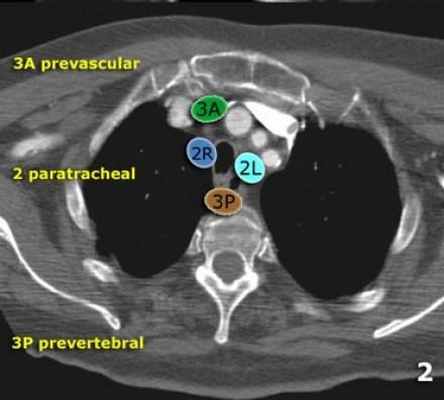

Верхние медиастинальные лимфатические узлы 2-4

2L Левые верхние паратрахеальные располагаются вдоль левой стенки трахеи, от верхнего края рукоятки грудины до верхнего края дуги аорты.

2R Правые верхние паратрахеальные располагаются вдоль правой стенки трахеи и спереди от трахеи до ее левой стенки, с уровня верхнего края рукоятки грудины до нижней стенки левой плечеголовной вены в зоне пересечения с трахеей.

3А Преваскулярные лимфатические узлы не примыкают к трахее как узлы 2 группы, а располагаются кпереди от сосудов (от задней стенки грудины, до передней стенки верхней полой вены справа и передней стенки левой сонной артерии слева)

3P Превертебральные(Ретротрахеальные) располагаются в заднем средостении, не примыкают к трахее как узлы 2 группы, а локализуются кзади от пищевода.

2R. Правые верхние паратрахеальные лимфатические узлы

Располагаются до левой стенки трахеи.

Верхняя граница: верхний край рукоятки грудины.

Нижний край: пересечение нижнего края плечеголовной вены с трахеей.

2L. Левые верхние паратрахеальные лимфатические узлы

Нижний край: верхний края дуги аорты.

На изображении слева представлены 2 лимфатических узла кпереди от трахеи, то есть 2R, так же виден небольшой преваскулярный лимфатический узел 3A группы.

3. Праваскулярные и превертебральные лимфатические узлы

Лимфатические узлы 3 группы не примыкают к трахее в отличии от лимфатических узлов 2 группы.

Они подразделюятся на:

3А кпереди от сосудов

3Р позади пищевода/превертебрально

Они не доступны при медиастиноскопии. 3Р группа может быть доступна при чреспищеводной эхокардиографии.

На изображении слева 3А узел в преваскулярном пространстве. Обратите внимание так же на ниже расположенные паратрахеальные узлы справа относящиеся к 4R группе.

2. верхние паратрахеальные лимфатические узлы: ниже ключиц , справа над пересечением нижнего края левого плечеголовного ствола и трахеи, а слева над дугой аорты

3. Преваскулярные и ретротрахеальные: кпереди от сосудов (3А) и превертебральные (3Р)